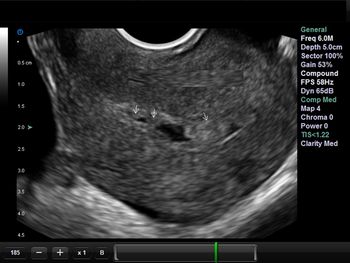

What's your diagnosis based on these images of the fetal neck?